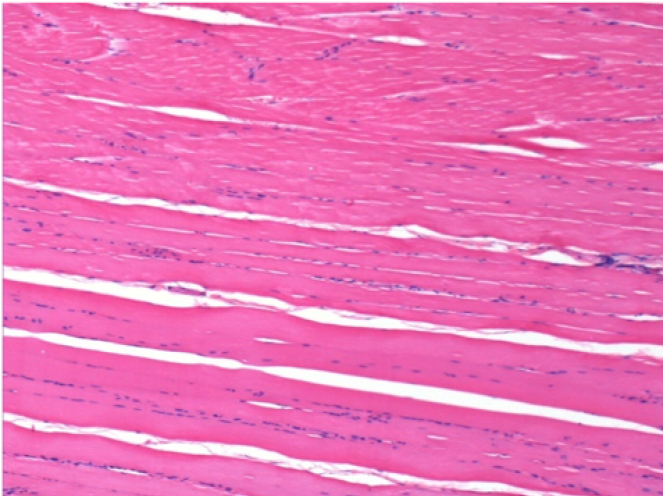

L:Pretibial-No treatment

10 days after Endopeel Injection 0.1ml in the right pretibial muscle.

Here you may see the formation of the vacuoles which are surrounded by lymphocytes. Vacuoles are different from tissue necrosis . The presence of lymphocytes is related to the permeability of the cell membranes.